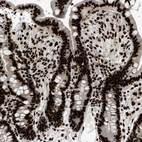

Immunohistochemical staining of human cerebral cortex, gastrointestinal, kidney and lymphoid tissues using Anti-LUC7L3 antibody HPA020017 (A) shows similar protein distribution across tissues to independent antibody HPA018475 (B).